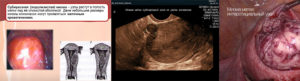

В зависимости от размеров и расположения узлов различают 3 разновидности миомы матки:

- интрамуральная или внутримышечная – располагается в середине мышечного слоя и характеризуется большими размерами;

- подслизистая – растет внутрь полости, что приводит к ее деформации;

- субсерозная – находится с внешней стороны и прорастает в брюшную полость.

Существует и отдельная разновидность болезни – миома «на ножке». Растет на узком или широком основании, соединяющем ее со стенками органа. Также может быть подслизистой или субсерозной, т. е. находиться снаружи или внутри маточной полости. Очень редко новообразование может располагаться в шейке.

Чаще всего болезнь можно обнаружить при гинекологическом осмотре по увеличению матки в размерах, утолщению или деформации ее стенок. Для определения места расположения и величины опухоли назначается УЗИ половых органов.

Согласно расположению новообразований различают такие виды: